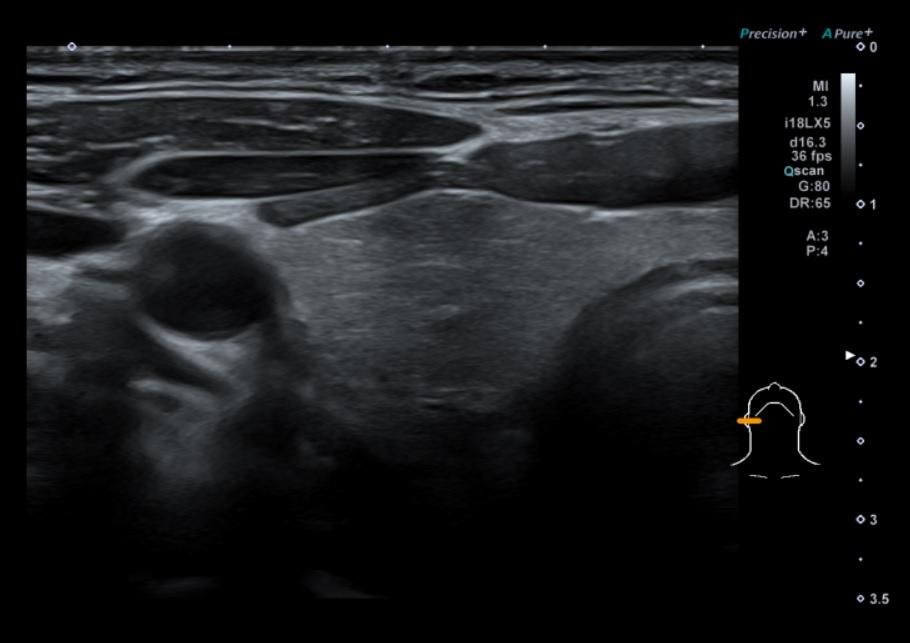

• 1번 째 사진